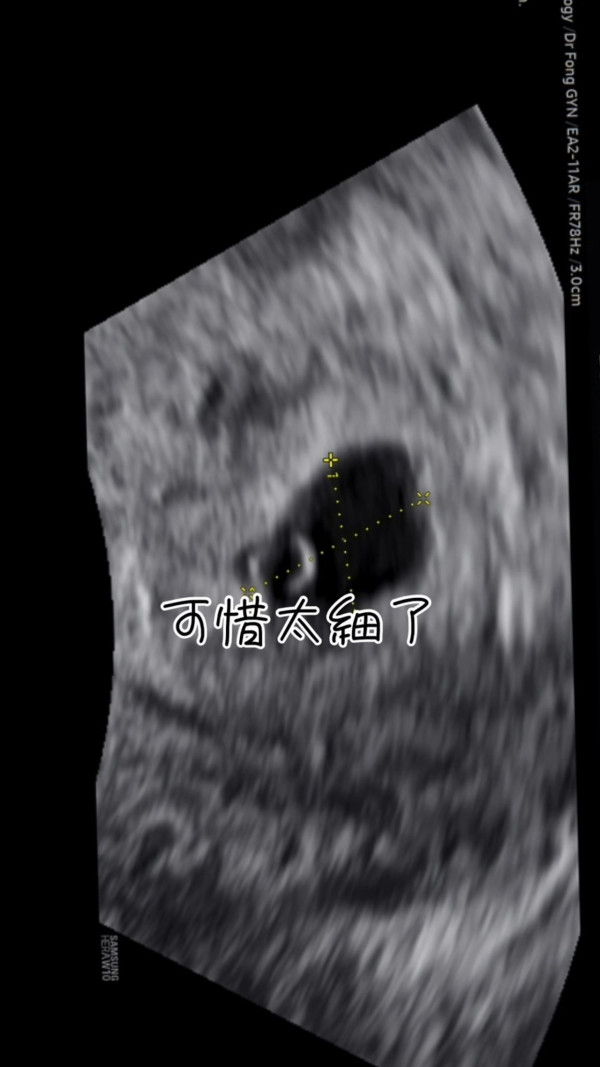

李清心只好耐心等待一星期後再檢查,不過等待的期間就令Katarina十分煎熬:「可惜(懷孕)周數太細喇,乜嘢都照唔到,聽唔到心跳,唯有休息一個禮拜等下次覆診睇吓有冇心跳啦。呢個禮拜真係好漫長,心情跌落谷底。」而她更晒出染有啡血及鮮血的衛生巾,表示持續有出血情況。